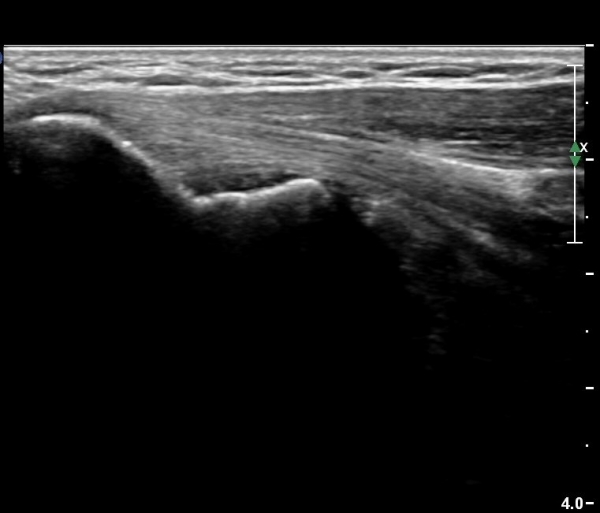

¿ä°ñµÎ Ⱦ´Ü¸é°Ë»ç¿Í Á¾´Ü¸é°Ë»ç¿¡¼­ ƯÀÌ ¼Ò°ß º¸ÀÌÁö ¾ÊÀ½(»çÁø ¾øÀ½)